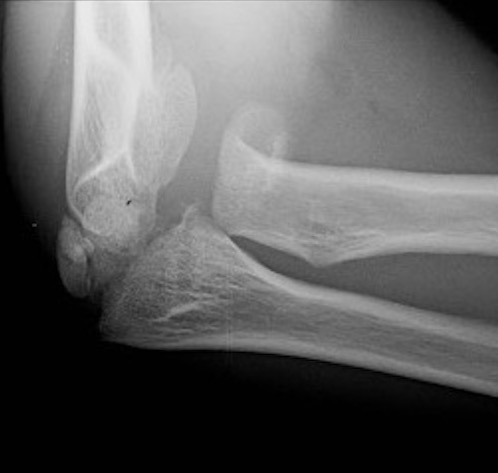

Xray

Displaced and angulated radial neck fracture

Radial neck fracture and olecranon fracture